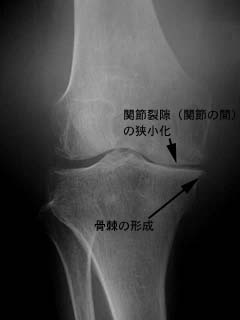

変形性膝関節症のレントゲン写真

右変形膝関節症の膝の正面から見たレントゲン写真です。

内側の関節面の透き間がなくなっています。これは関節の間にあった軟骨がすり減ってしまったためです。変形が高度になると骨棘(骨のトゲ)も出てきます。